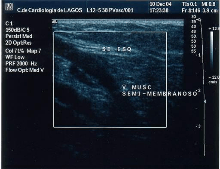

The small saphenous vein (SSV), runs along the posterior aspect of the leg as far as the popliteal region, in the upper calf. Here it enters the popliteal space which is located between the two heads of the gastrocnemius muscle where it usually drains above the knee joint in the popliteal vein or a little less often in the great saphenous vein (GSV) or other deep muscular veins of the thigh.[52] The use of ultrasonography has allowed a number of variations to be shown at this level; when no contact is made with the popliteal vein it might be seen to drain in the GSV, at a variable level; or, it may merge with the Giacomini vein and drain in the GSV at the superior 1/3 of the thigh. It can also but rarely, drain in the vein of the semimembranosus (thigh muscle) (shown below). Usually though, it connects with a perforator vein at its middle 1/3.[22] To check for insufficiency, the Paraná maneuver is very useful.[35]

![]() Insufficiency from the SSV flooded by the vein of the semimembranosus muscle |

![]() SSV variant draining in the vein of the semimembranosus muscle |